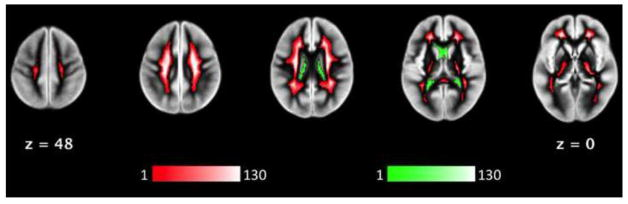

As a potential aid for evaluating the masks we obtain, I'm including here for reference the subject-wise voxel inclusion frequency map for WM and CSF masks in the Muschelli study.

image

(from Muschelli et al., 2014)